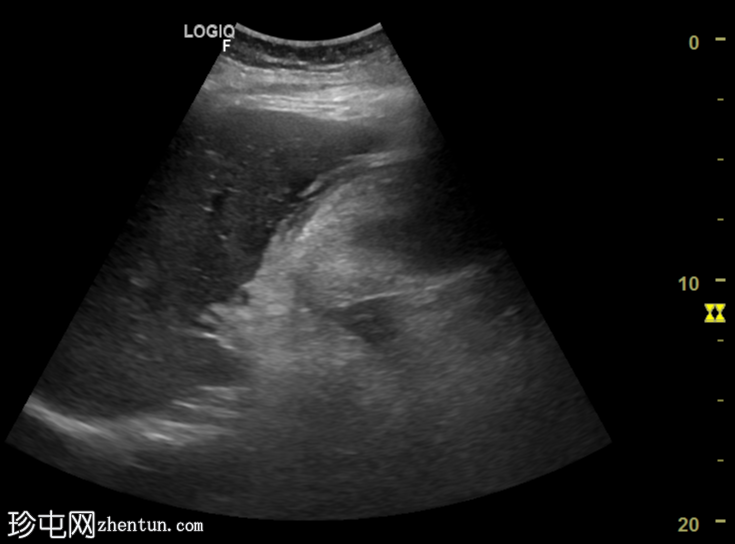

横切面

胆囊扩张,充满回声不均的异质性高回声物质(高回声、等回声、低回声),并可见漂浮回声。

可见胆囊周围水肿,胆囊壁不对称增厚,呈局灶性断裂,胆囊壁内可见强回声灶和强回声线(可能为气体腔)。

总体表现提示复杂性胆囊炎(坏疽性)。